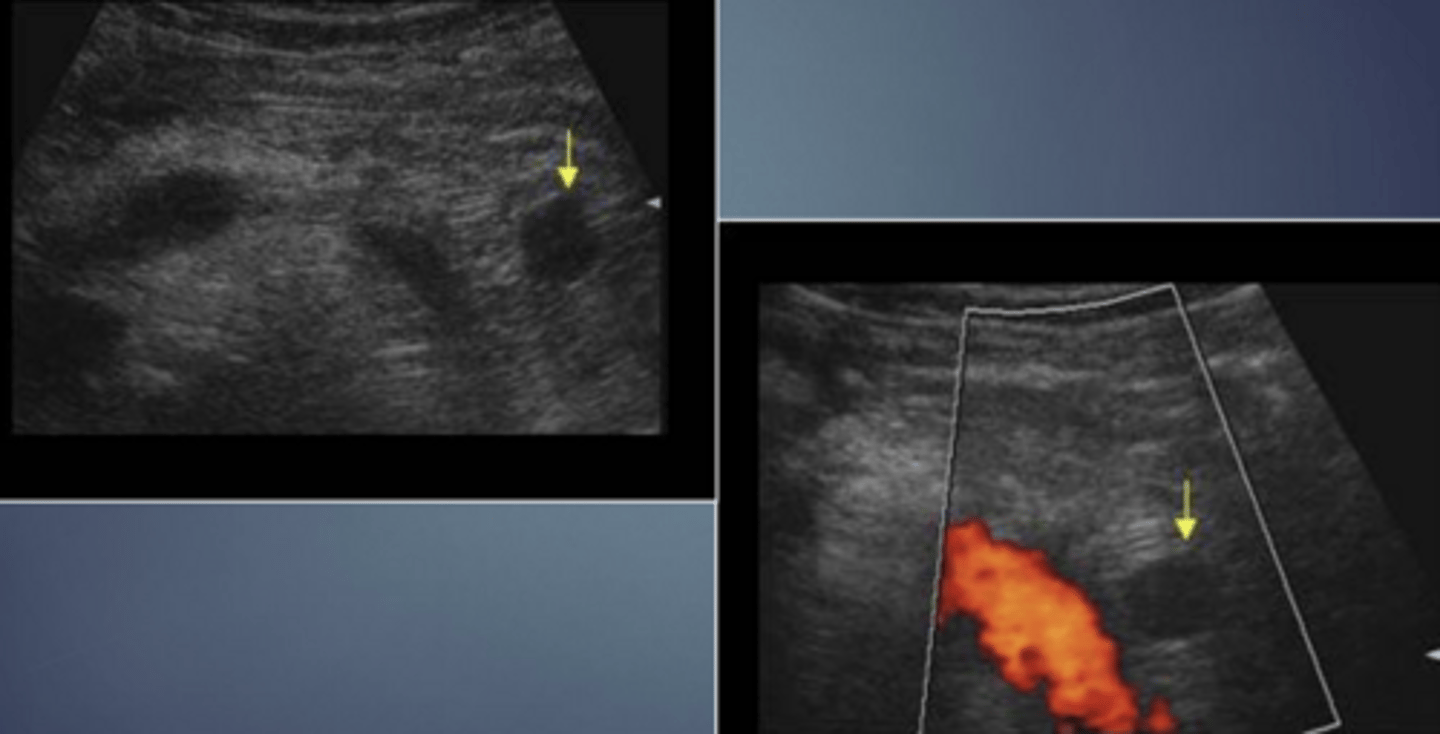

Islet Cell Tumor (Adenoma) Sonographic Appearance

-generally homogenous and solid

-frequently hypoechoic

-larger tumors may become moderatly echogenic

-calcifications and fluid areas seen in larger lesions

-solid masses are generally functional while those w/ cystic areas of necrosis are generally non functional

-small 1-2cm tumors difficult to identify

Islet Cell Tumor (Adenoma)